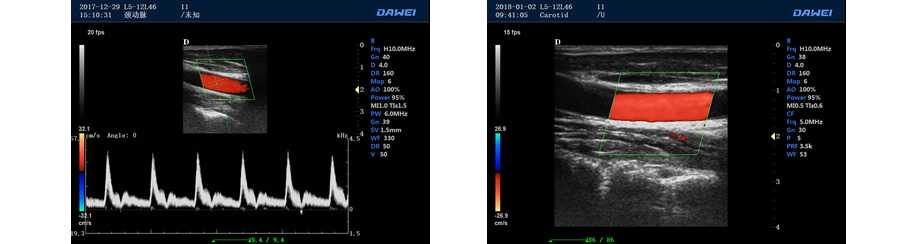

多普勒模式

具有PW脈沖波多普勒和CW連續波多普勒

取樣容積大小,可視可調

采樣角度校正:-30-80度

脈沖重復頻率多段可調

實時自動多普勒包絡描述及自動測量與分析

外周血管 多普勒血流測量與分析